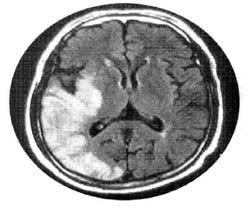

<Áß´ë³úµ¿¸Æ

ÁÖÁÙ±âÀÇ ³ú°æ»ö> <°æ¸·ÇÏ

Ç÷Á¾ÀÇ ¼ö¼ú ÈÄ CT>